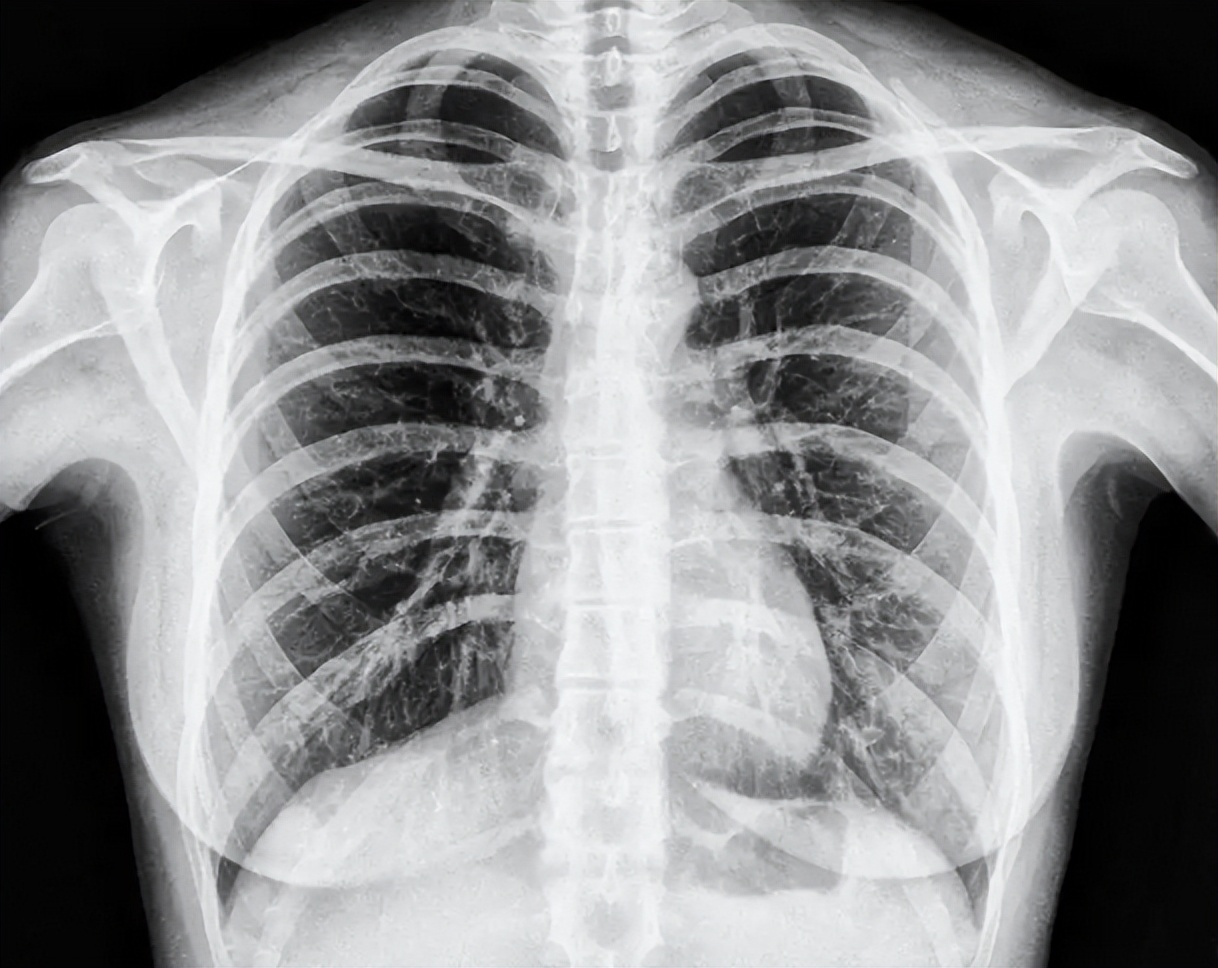

除此之外,普通体检往往只做胸片。普通X线胸片可检出的肺结节需大于1厘米,而低剂量螺旋CT却能发现3毫米以下的微小肿瘤。常规体检的“盲区”,也导致不少高危人群没有得到及时筛查。

肺癌筛查如何做?三招精准识别、争取生命时间低剂量螺旋CT。是目前国际公认的肺癌早筛优选方案。对比普通胸片,其能发现3-5毫米的微小结节,大大提高了早期癌症检出率。强烈建议60岁以上、有长期吸烟史或职业暴露人群每年筛查一次。